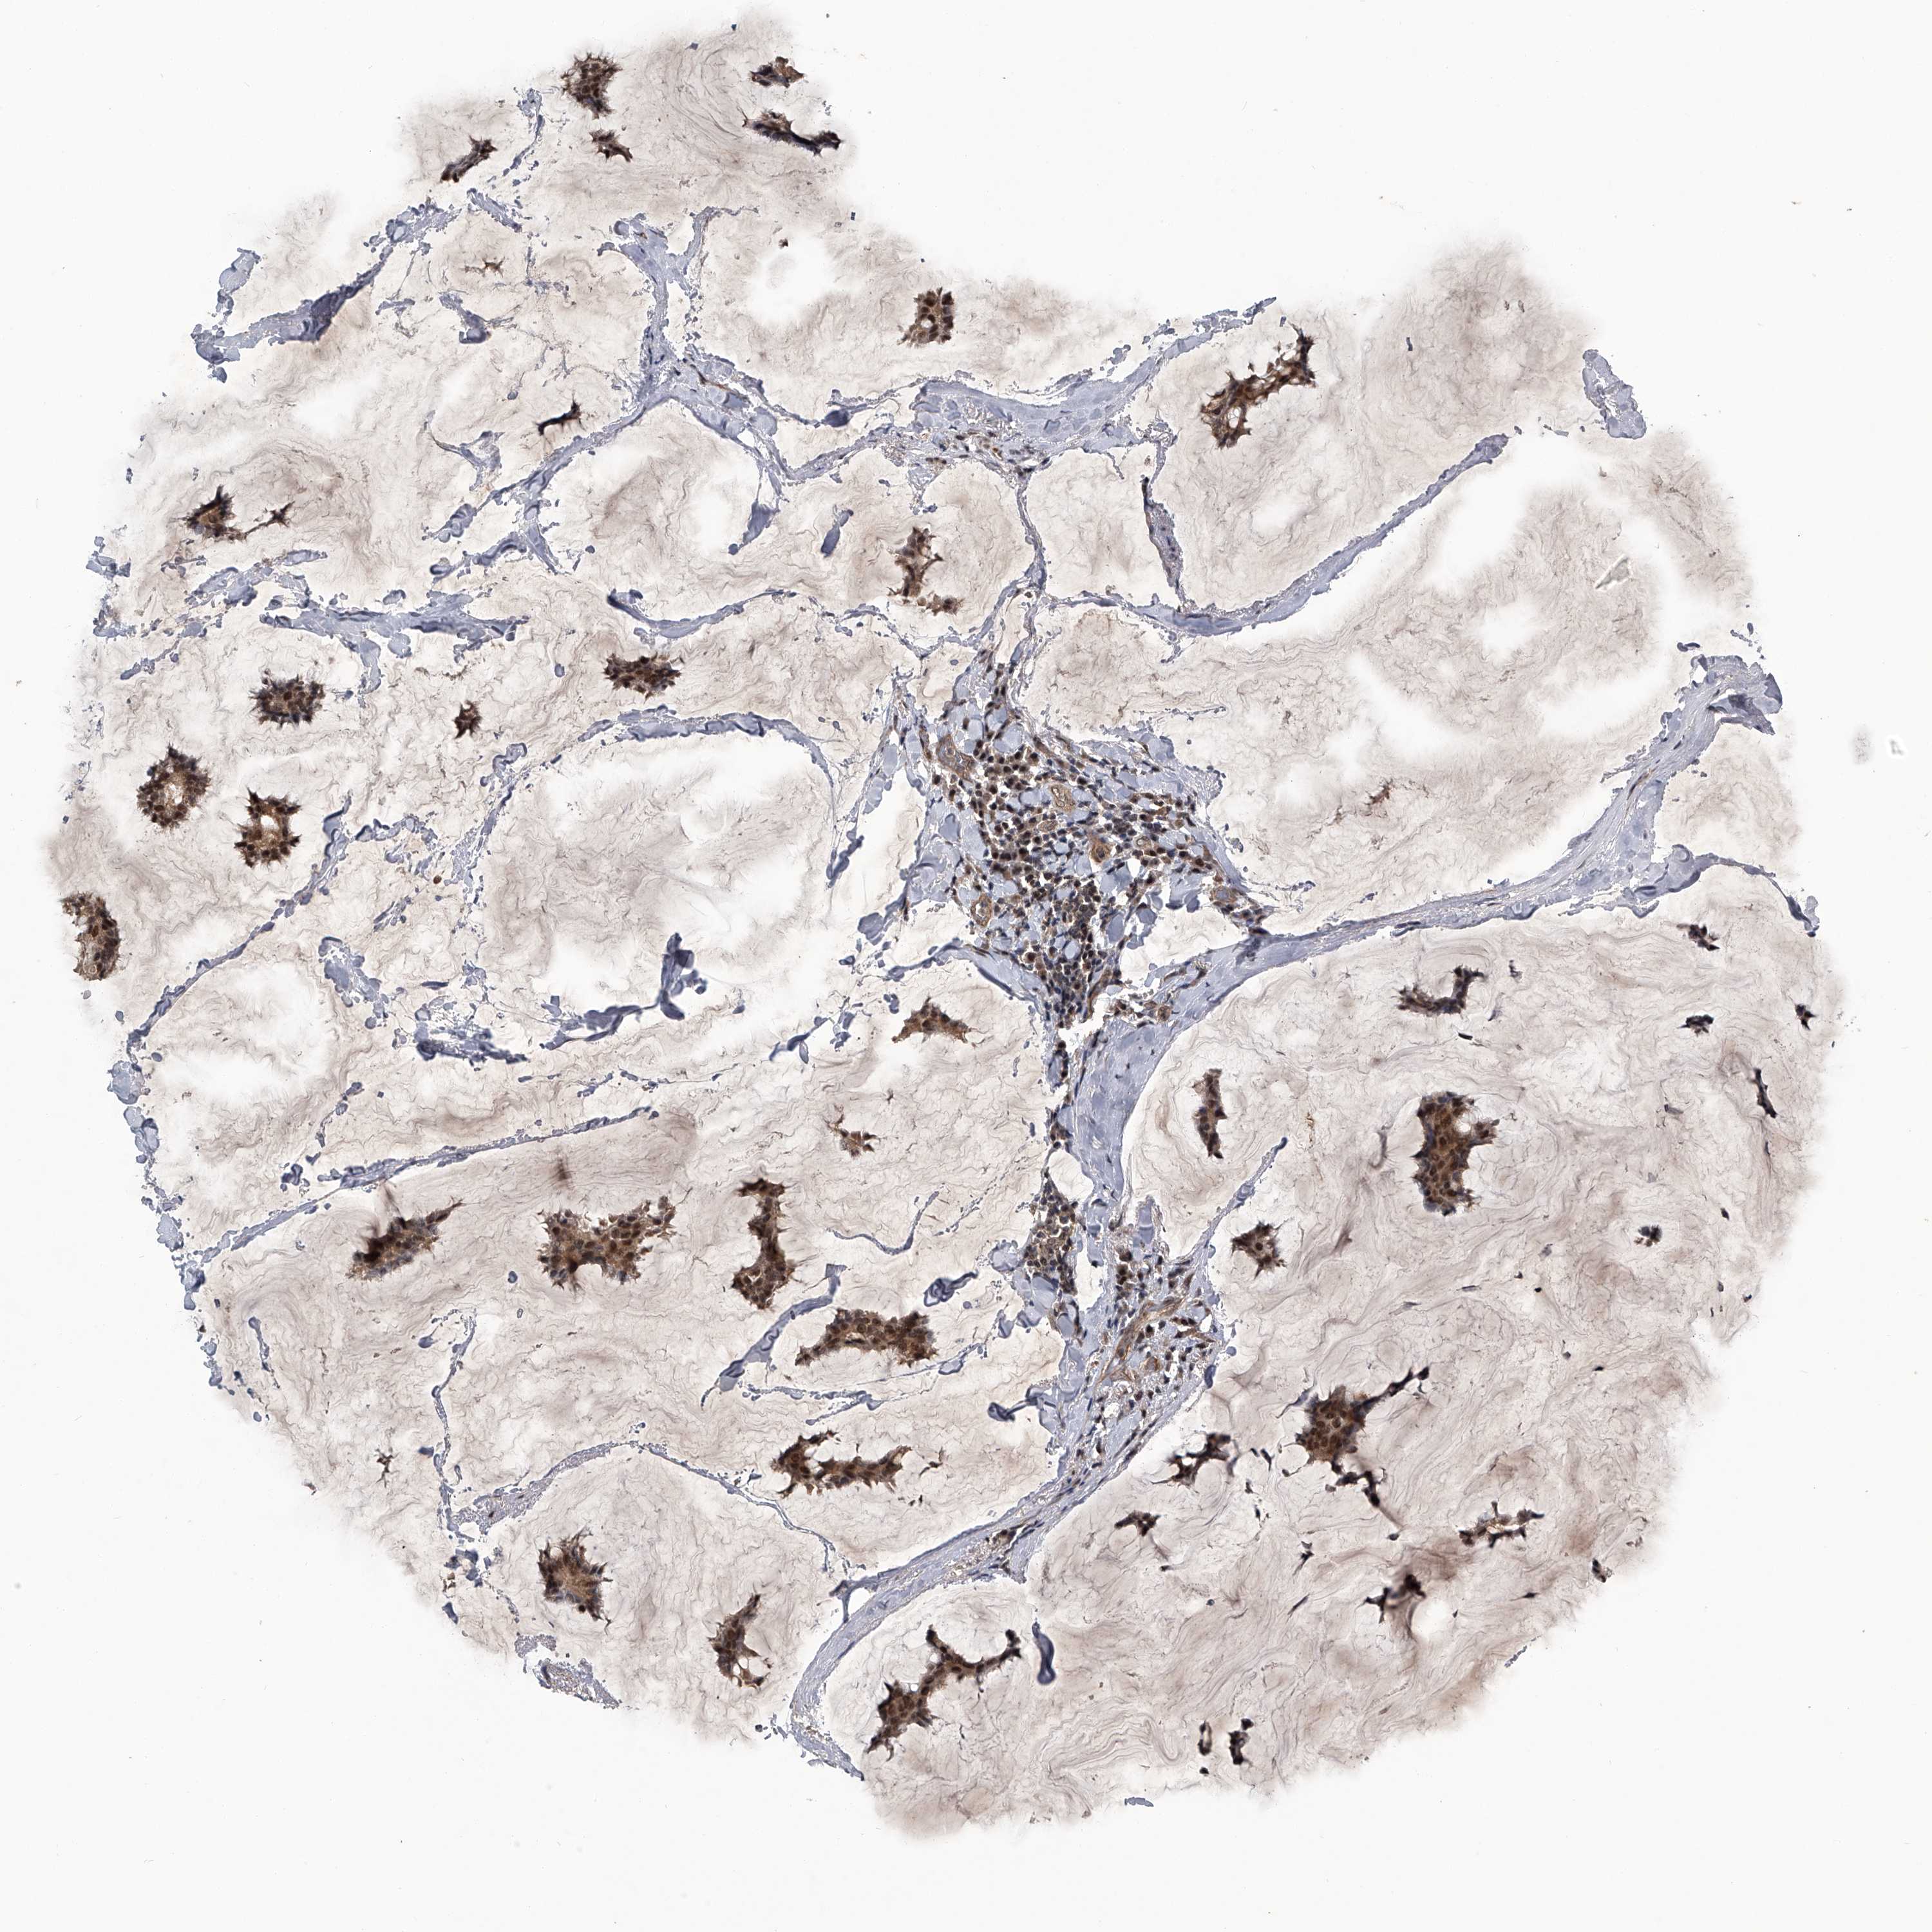

CANCER BREAST CANCER Show tissue menu

BRCA TCGA BRCA VALIDATION PROTEIN EXPRESSION

Breast cancer

Human cancer

SLC12A8 is not prognostic in Breast Invasive Carcinoma (TCGA)

Average pTPM 8.1

Number of samples 1022